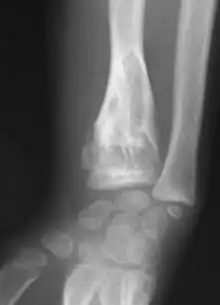

Abnormal bone growth such as shortening or thickening and deformity may be observed in patients of Ollier disease. These bone lesions are visible at birth using radiography but are usually not screened or examined for until clinical manifestations present during early childhood. However, some patients may exhibit no signs of any symptoms.[1] One study found thirteen to be the mean age of diagnosis in patients with Ollier disease. In an X-ray, there would normally be the presence of several homogeneous lesions of an oval or elongated shape with bone edges that are slightly thickened.[3] With age, these lesions may calcify and appear as diffusely minute spots or stippled. Fan-like septations or streaks would be indicative of the presence of several enchondromas. Early detection and consistent and repeated monitoring is important in order to prevent and treat any potential bone neoplasms.

X-ray showing enchondromas localized in the lower part of the radius of a 37-year-old patient affected with Ollier disease